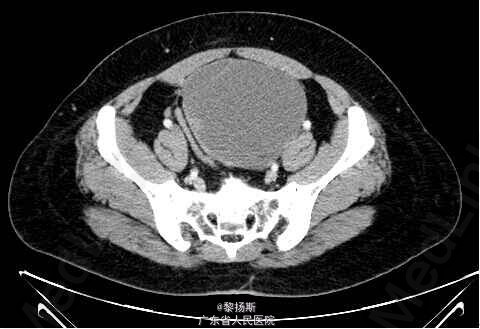

女性,42岁,”发现盆腔包块2年”,无腹痛,无异常阴道流血;自述10年前曾因“盆腔炎” 在外院手术治疗,切除一侧附件,具体不详,有子宫肌瘤病史。

查体:生命体征平稳。腹部可触及包块。影像学:左侧附件区见一囊实性占位,边界清晰,囊性成分较多,增强内可见分隔,囊壁强化明显,并可见强化壁结节。实性成分强化明显。盆腔未见明显肿大淋巴结,未见明显积液。鉴别诊断:卵巢浆液性囊腺癌:也表现为附件囊实性包块,可见分隔,亦可见强化壁结节,鉴别诊断欠困难,有文献称CA125较透明细胞癌升高。病理示:左侧卵巢透明细胞癌。

诊断:左侧卵巢透明细胞癌

原发性卵巢肿瘤分为三种类型,既上皮肿瘤、性索间质肿瘤、生殖细胞肿瘤,卵巢上皮肿瘤依据上皮细胞的类型又分为浆液性癌、粘液性癌、子宫内膜样癌及透明细胞癌。卵巢透明细胞癌是一种起源于苗勒管的卵巢上皮恶性肿瘤,约占卵巢上皮癌的5%,恶性程度高。多发生于成年女性,几乎所有患者诊断时年龄均为25岁以上,临床表现以腹部肿块最常见。透明细胞癌影像上以囊实性肿块多见,并以囊性部分为主,内可见分隔,并可见强化壁结节。实性部分表现为腔内突起,形态不一,乳头或息肉状,部分呈类圆形。肿瘤血供丰富,动脉期明显强化,静脉期及平衡期仍持续强化。难与浆液性囊腺癌鉴别。有文献报导,与浆液性囊腺癌比较,卵巢透明细胞癌具有不同的临床及分子生物学特点:①术前血清CA125值较低,腹腔积液出现几率少,术后残余肿瘤较小。②肿瘤单侧发生,乳头状突起呈分级分支模式。③合并子宫内膜异位症,尽管不特异,也应考虑该肿瘤可能。④免疫组化:Wilms瘤I基因(WT1)和雌激素受体(ER)表达多呈阴性。术前诊断比较困难,确诊主要依靠病理学检查。